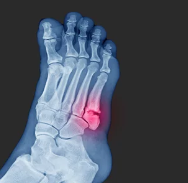

발가락 골절은 발가락 뼈가 충격을 받아 부러지거나 금이 가는 상태를 말합니다. 발가락은 생각보다 작고 약한 구조를 가지고 있어 부상이 잦으며, 골절의 정도와 위치에 따라 치료와 회복 시간이 달라집니다.

발가락 골절의 종류

- 단순 골절: 뼈에 가벼운 금이 가거나 뼈가 부분적으로 부러진 상태로, 비교적 치료가 간단한 경우입니다.

- 복합 골절: 뼈가 여러 조각으로 나뉘거나, 뼈가 관절 밖으로 튀어나온 경우로, 복합적인 치료가 필요할 수 있습니다.

발가락 골절이 발생하면 즉시 통증이 나타나고 붓기나 멍이 들 수 있으며, 발가락을 움직이는 데 어려움을 겪을 수 있습니다.